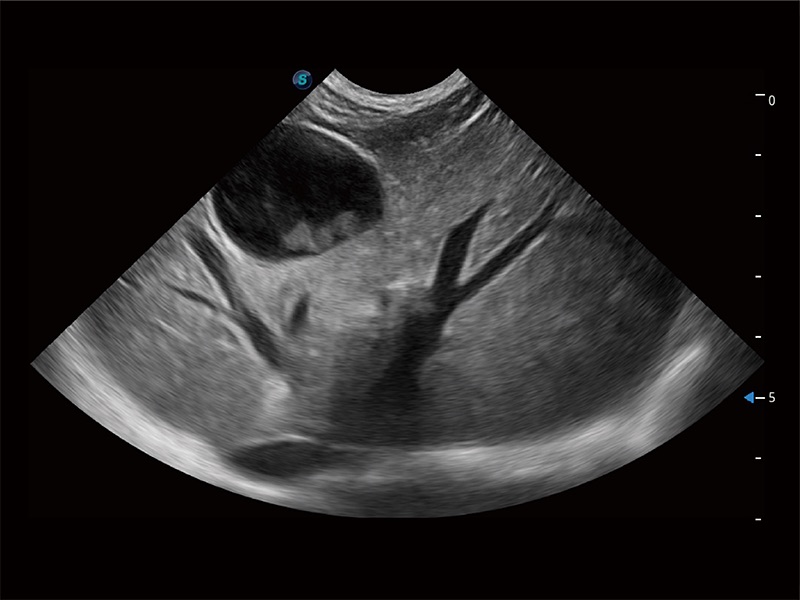

一键自动识别膀胱壁及自动测量膀胱容积,不受膀胱形状和大小的限制,帮助医生快速精准获得测量的数据。